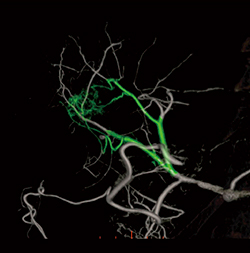

FPFLを起動すると,MIPおよびVR画像,そして各断面画像が自動表示される。その後,腫瘍濃染位置をROIで囲みクリック操作すると,栄養血管と思われる信号を自動検出し,VR画像上で緑色に表示する(図4)。血管自体の描出能を妨げることを危惧し,あくまでも色のみを変化させ補助ラインなどは表示しない。かつFPFLによる探索結果とともに,MIPやVR画像ならびに各断面画像を同時表示することにより,術者自身が栄養血管に関して総合的な判断が行えるように画像がレイアウトされている(図5)。

図4 FPFLによる栄養血管の探索結果表示